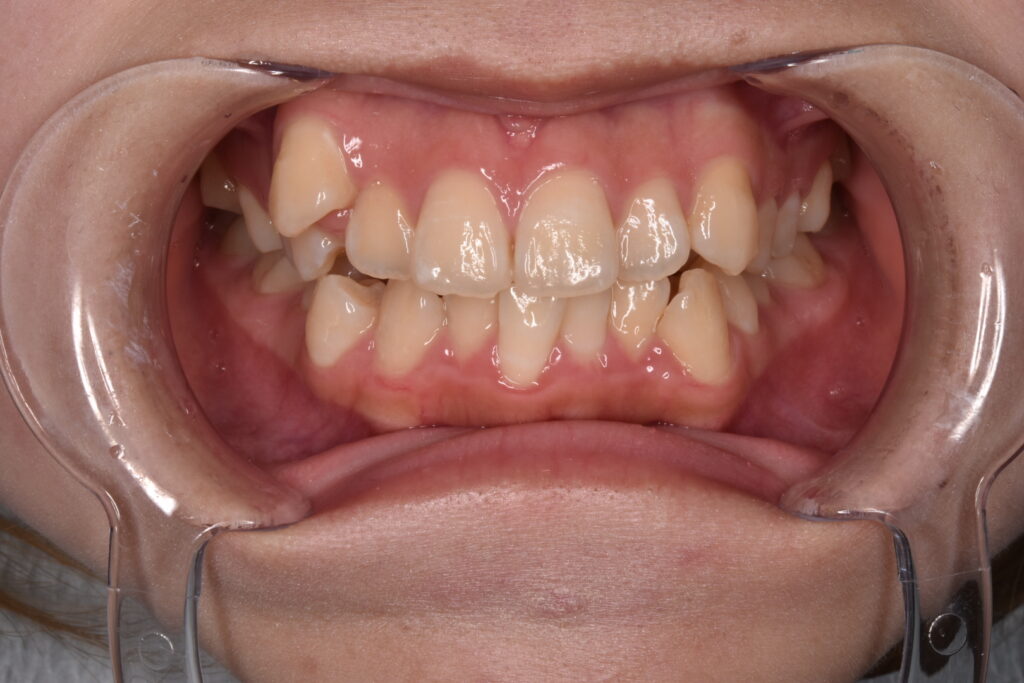

現状38枚目(矯正開始後10ヶ月)

現在矯正開始から38週経過し38枚目になっています。追加アライナーなし、順調に経過しています。八重歯感もだいぶ改善してきましたね。噛み合わせは本人様は全然気にならない様ですが最後に調整していきます。追加アライナーとゴムかけなどです。